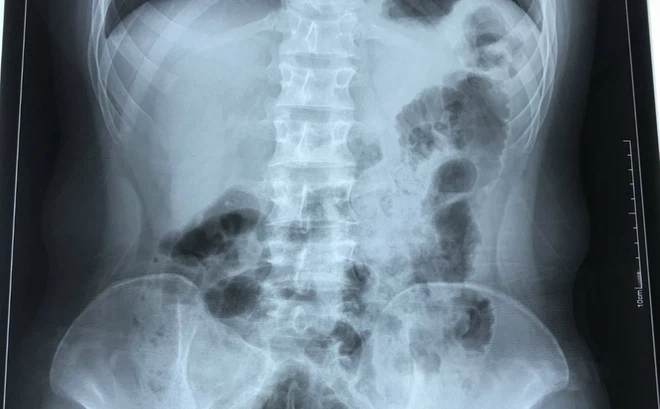

Phim chụp X-quang của bệnh nhân cho thấy tình trạng phủ tạng đảo ngược với trái tim nằm bên lồng ngực phải (Ảnh: BVCC)

Đặc biệt, bác sĩ phát hiện trái tim của nam thanh niên nằm bên lồng ngực phải, ở vị trí đảo ngược so với người bình thường. Gia đình cho biết, trái tim và các tạng trong cơ thể H. đều nằm ở vị trí đối lập so với mọi người.